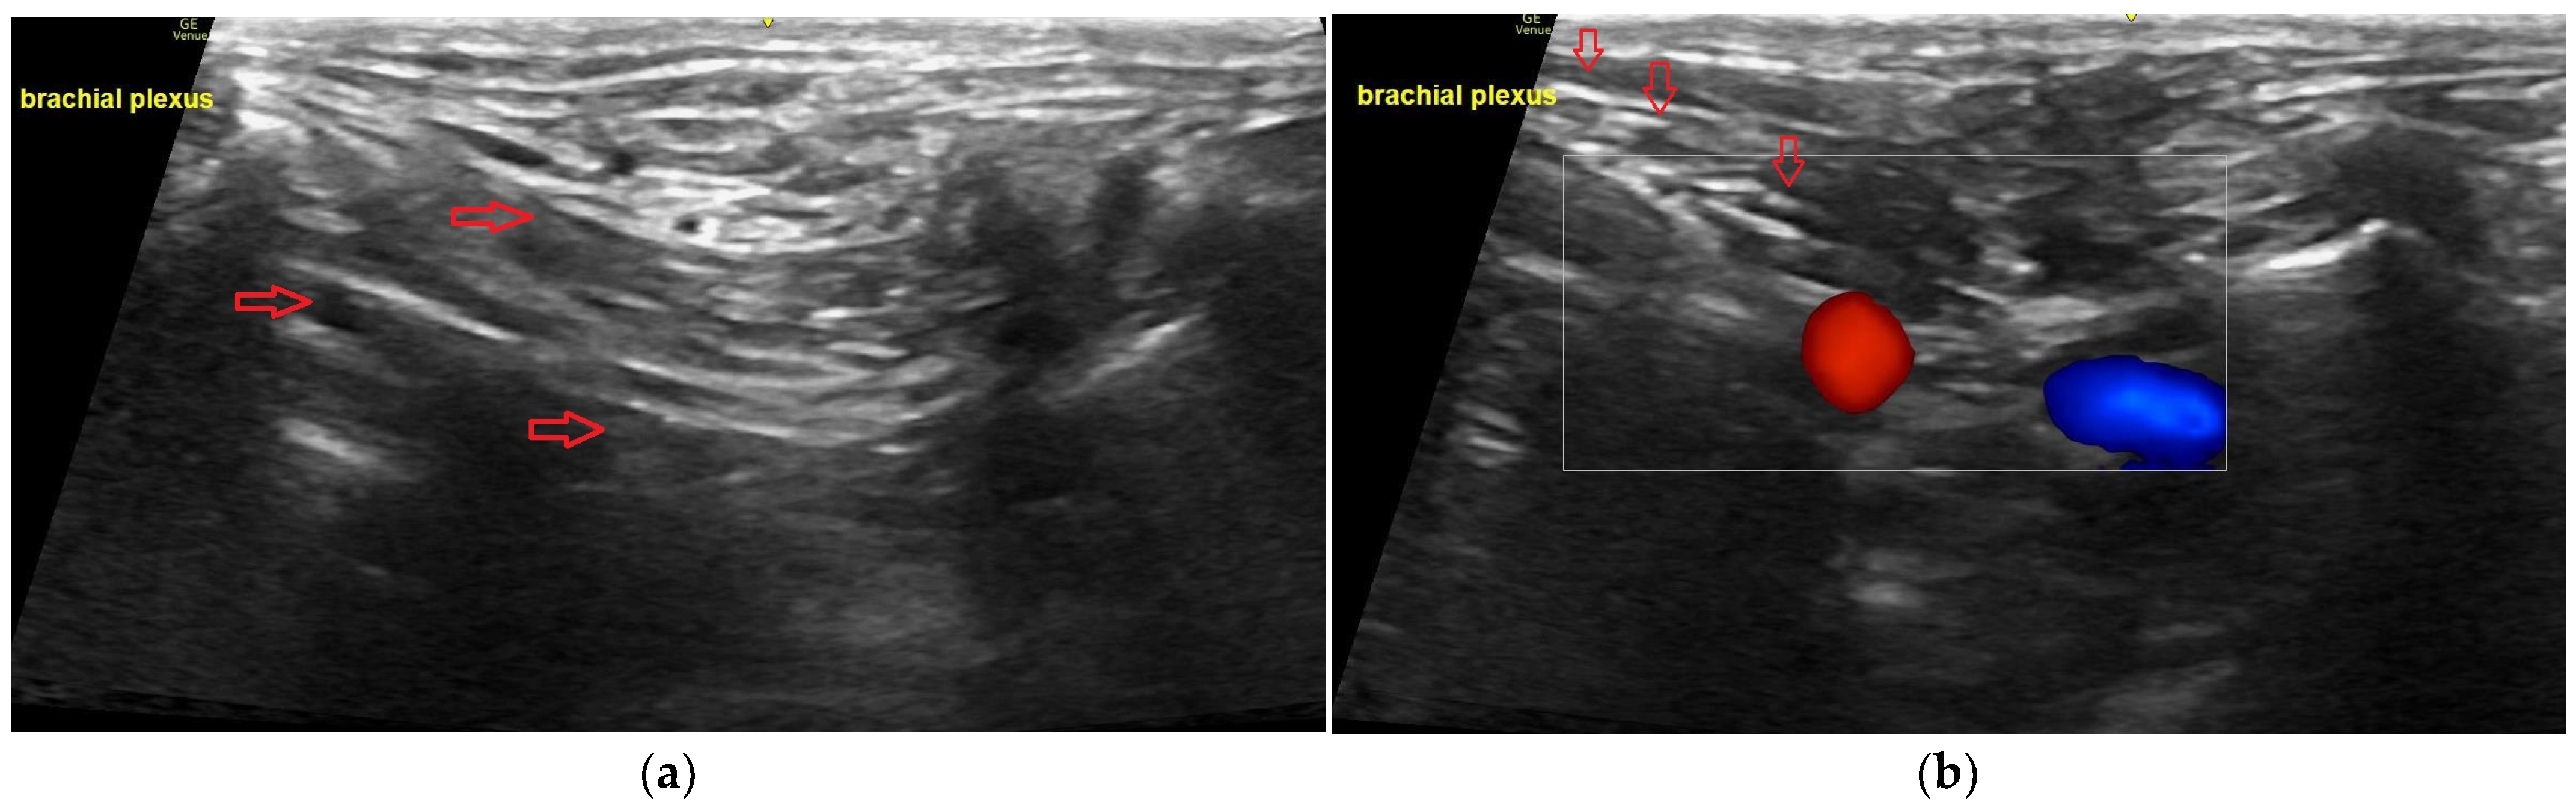

7.2. Brachial Plexus Block

7.3. Radial, Ulnar, Median and Musculocutaneous Nerves Block (RUMM)